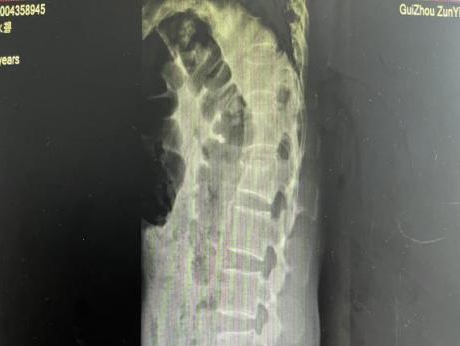

12月17日,贵州航天医院第88次晨读会由我院骨一科主任、副主任医师陈明勇作学术交流,他以“肱骨近端骨折并肩关节脱位的手术治疗”为题,全面讲解了该损伤的手术策略、术中血供保护理念及内侧支撑重建技术等内容,并通过多个典型病例图文资料分享了从损伤机制分析、手术步骤实施到术后随访评估的完整过程与关键细节,为临床处理此类复杂骨折提供了较为全面的技术参考,有助于在手术规划中结合个体情况开展针对性治疗。 贵州航天医院 骨科专家简介 陈明勇 骨一科主任,副主任医师 临床擅长:从事创伤骨科工作约20年,对骨缺损、骨不连、骨肿瘤、肢体畸形等的肢体矫形重建及功能重建,慢性化脓性骨髓炎的根治治疗、糖尿病足的保肢治疗、快速康复理念(ERAS)下的老年骨折的诊治,四肢复杂骨折的诊治,四肢骨折等微创手术治疗具有丰富的临床经验。 2004年毕业于遵义医学院临床专业,曾在中国人民解放军总医院、广西医科大学第一附属医院、上海第六人民医院骨科进修。中国中西医结合学会骨伤科专业委员会横向骨搬移治疗糖尿病足及微血管网再生学组首届委员,遵义市医学会创伤分会常务委员。 瞿 晖 骨科党支部书记,骨二科主任,副主任医师 临床擅长:对骨科的常见病、关节外科、脊柱外科及运动医学疾病的诊治具有丰富的临床经验,熟练掌握骨科手术操作技术。 毕业于遵义医学院临床医学系,2005年前往广州中山大学第一附院骨显微医学部进修学习,2011年前往成都华西医院进修学习,并多次在省内外学习骨科相关知识,是中华医学会骨科分会会员。 赵小锋 中共党员,骨二科副主任,副主任医师 临床擅长:从事骨科临床工作11年,对骨科常见病、多发病诊疗有较为丰富的临床经验,擅长脊柱相关疾病诊断及治疗,尤其是颈、腰、腿疼痛疾病诊断及治疗,擅长胸腰椎骨折微创经皮穿刺内固定术、经皮穿刺椎体成形术、经皮穿刺脊柱内镜下腰椎间盘摘除术、单纯开创腰椎间盘摘除术、腰椎滑脱复位椎间植骨椎融合内固定术、腰椎管狭窄减压融合内固定术及人工髋、膝关节置换术等。 2012年毕业于遵义医学院外科学专业硕士研究生,2019年参加“遵义市115医学人才精英计划”于上海交通大学第一附属医院培训学习,2023年于北京大学第三人民医院脊柱外科进修学习,曾获得遵义市优秀医师荣誉称号。 遵义市手外科第一届委员,遵义市医学会创伤分会第一届委员,遵义市医学会创伤分会第二届委员,贵州省康复医学会第三届脊柱脊髓专业会委员,遵义市医学会烧伤与整形外科学分会委员,发表论文5篇,其中国家级核心期刊1篇,SCI论文1篇,主持市级课题1项并结题,参与市级课题2项。 赵兴东 骨科主任医师 临床擅长:擅长骨科的常见病及各种创伤、四肢骨折创伤修复、骨感染、手足疾病的诊治和手足体表畸形的矫形整复,熟练掌握骨科四肢骨病及创伤的手术操作技术,尤其在四肢关节复杂性损伤、手足外伤、组织缺损创面、难治创面的皮瓣修复方面及平足、高弓足矫形方面及四肢慢性疼痛诊治、康复方面具有丰富的临床经验。 硕士研究生,毕业于遵义医学院临床外科系,2015年前往山东省立医院手足外科进修学习;遵义市医学分会创伤分会第一、二届委员,遵义市手外科医学会第二委届员会常务委员;在省级及省级以上期刊发表文章9篇,参编著作2部,参与主持并完成市级课题1项,参与市级课题2项、省级课题1项。 张艳金 中共党员,骨科副主任医师 临床擅长:从事骨外科工作16年,对复合伤、多发伤的救治、四肢骨干骨折、关节周围骨折、骨肿瘤、骨髓炎等诊治具有丰富的临床经验。 中共党员,硕士研究生,2006年本科毕业于山西医科大学第二临床医学院,2011年研究生毕业于北京军区总医院;在“老年COPD患者合并髋部骨折的诊治”国际合作课题组研究两年,在老年髋部骨折的诊治方面具有丰富的经验,并发表论文6篇;主持遵义市级课题1项,承担遵义医科大学的临床教学工作,获得遵义医科大学优秀带教老师荣誉。编撰有《骨科疾病诊疗精粹》一书,开展2项新技术,编撰地方规范《务川自治县创伤骨科常见疾病诊疗规范》一书。 张俊凯 骨科副主任医师 临床擅长:从事骨科临床工作28年,对创伤骨折、骨感染、骨缺损、骨不连等外科诊治,四肢骨折的微创手术治疗,四肢复杂骨折(如关节内粉碎性骨折、多发骨折等)的损伤控制及手术治疗等具有丰富的临床经验。 1995年毕业于遵义医学院临床专业,2009年前往复旦大学附属医院骨科进修1年。 卢懿明 中共党员,骨科副主任医师 临床擅长:从事骨科工作18年,对创伤骨折、四肢骨折的微创手术治疗、四肢复杂骨折(如关节内粉碎性骨折、多发骨折等)的损伤控制及手术治疗,尤其是髋部骨折的PFNA等微创技术,踝关节骨折、膝关节周围骨折的Mipo微创技术等具有丰富的临床经验,开展了4项新技术,发明6项新型专利技术。 2005年毕业于遵义医学院临床专业,2017年,前往南方医科大学第三附属医院骨科进修半年,回院后运用Mipo技术对骨干骨折及干骺端骨折的治疗技术,同时积极开展骨盆骨折、髋臼骨折腹直肌外侧切口的应用;发表了多篇专业论文,经常参与省内外学术交流会授课,获得医院荣誉称号多个。 邬夏荣 骨科副主任医师 临床擅长:从事骨科工作16年,对四肢复杂骨折、骨肿瘤的诊治,尤其是足踝创伤、慢性踝关节损伤、平足症等诊疗具有丰富的临床经验。 2006年毕业于遵义医科大学临床医学专业,曾在陆军军医大学西南医院进修学习,发表多篇骨科学术论文。 余德怀 中共党员,骨科副主任医师 临床擅长:从事骨科工作10余年,对运动医学、骨关节、脊柱外科常见病、多发病的诊治具有丰富的临床经验。 硕士研究生,2011年毕业于遵义医学院临床医学专业,曾前往遵义医科大学附属医院运动医学专业进修学习;是贵州省医学会运动医学分会青年委员,西部关节镜联盟委员;发表多篇骨科学术论文。 冯 乾 骨科副主任医师 临床擅长:从事骨科工作近20年,熟练掌握骨科多发病及常见病的诊治,尤其对脊柱退变性疾病的诊断及治疗具有丰富的临床经验,主要研究脊柱微创相关治疗方式,能熟练开展椎间孔镜及UBE。 曾前往北京大学第三医院进修学习疼痛及椎间孔镜、首都医科大学友谊医院专业进修脊柱内镜;是贵州省康复医学会第三届脊柱脊髓专业委员会委员;发明专利3项、发表脊柱外科专业论文多篇。 贵州航天医院骨科简介 基本情况 贵州航天医院(原3417医院)骨科组建于1968年,前身是以创伤和断肢(断指)再植闻名于世的上海市第六人民医院骨科,中国断肢(断指)再植的奠基者、中科院院士陈仲伟等专家莅临科室指导医疗和教学,并在70年代开展了贵州省首例断肢(断指)再植手术。组建50余年来,诊治患者已逾百万,挽救了无数的伤病员,成为了保障遵义地区人民群众健康的重要支撑。 经过几代人的不懈努力,今天的骨科,已由创伤骨科发展至骨病、骨肿瘤、骨结核等领域,现有脊柱外科、关节外科、四肢创伤、手足外科四个亚专科,成为了集医疗、教学、科研于一体的综合学科,是贵州省临床重点专科、遵义市临床重点专科、遵义市骨科临床医学中心、遵义市基层骨科专科联盟理事长单位。 科室目前开放床位110张,共有医护人员50余人,副高级以上专家18人,硕士研究生15人。拥有一流骨科医疗设备多台,每年不定期选派优秀技术骨干到全国各大知名医学院校进修、学习、参观、交流,并邀请国内、国外知名专家教授来院进行交流、指导,通过不断引进国内外先进的诊疗技术,科室医疗技术水平稳步提升,为广大人民群众提供了优质的医疗服务。 专科特色 骨一科 (一)骨缺损、骨不连的肢体与功能重建 胫骨横向骨搬移技术治疗糖尿病足: (二)慢性骨髓炎的根治治疗 (三)肢体缺血性疾病如糖尿病足、脉管炎的保肢治疗 (四)皮瓣修复 (五)复杂创伤的治疗 (六)老年髋部骨折及小儿骨折快速手术 老年髋部骨折: 骨二科 (一)胸腰椎骨折微创经皮椎弓根螺钉固定术 (二)老年性骨质疏松性患者腰椎滑脱脊柱内固定术(骨水泥螺钉) (三)V形双通道脊柱内镜技术(VBE)腰椎融合术治疗腰椎退行性疾病 (四)老年性骨质疏松性骨折(PVP/PKP)术 (五)人工髋关节置换术 (六)双侧股骨头坏死人工全髋关节置换 (七)右侧全髋置换术后假体周围骨折翻修 (八)人工膝关节置换术 (九)人工膝关节假体松动翻修 (十)关节镜技术 传统手术切口 关节镜技术切口 诊疗范围 骨一科 1.四肢创伤、矫形。 2.手、足踝外科。 骨二科 end